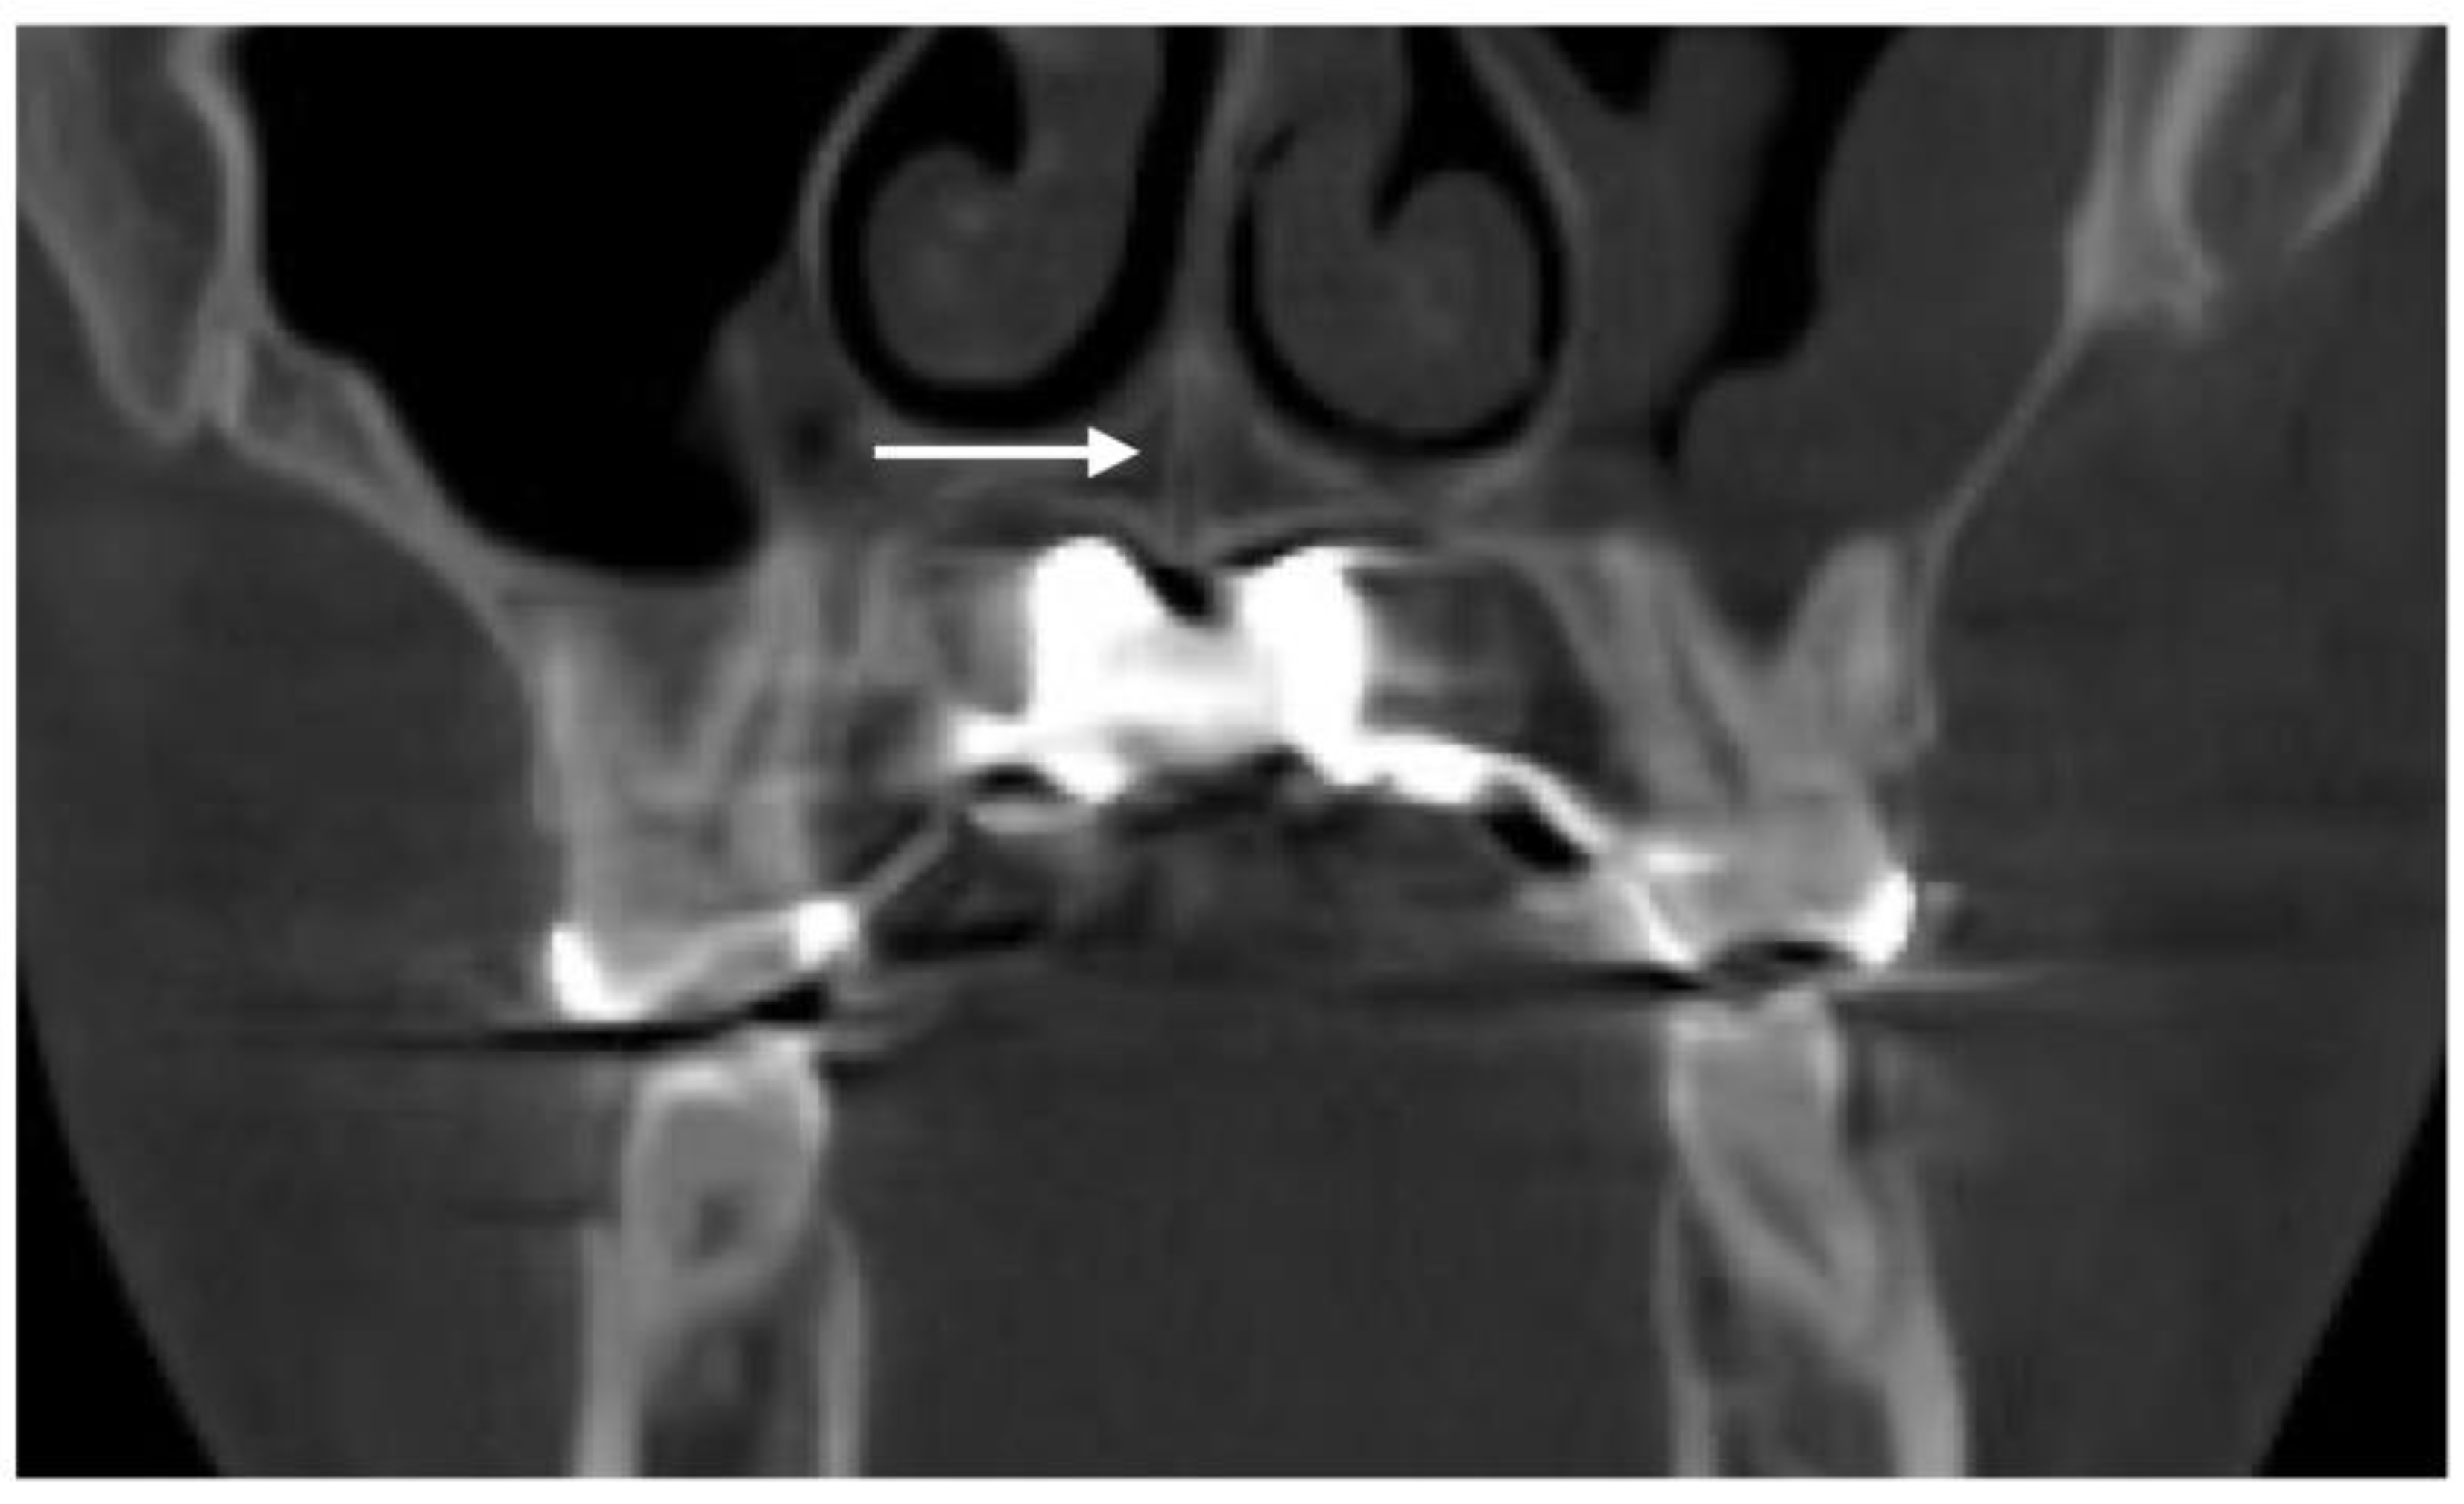

The 3D-guided midpalatal piezocorticotomy procedure and the custom MARPE positioning was undergone under topical anesthesia—20% Benzocaine topical anesthesia and 0.5% 1:200k epi Marcaine infiltration anesthesia. The piezocorticitomy cuts were performed immediately after anesthesia onset with the Mectron piezotome (Mectron, Hilliard, USA) and individually designed based on the 3D-printed piezocorticotomy guide. The ULD CBCT of the maxillary area was taken to confirm the depth and the location of the piezocorticotomy along with the custom MARPE screw positioning (Fig. 2).

Figure 2. Coronal view of the nasal base floor at the level of maxillary first molars depicting the location and depth of the piezocorticotomy incision and its relationship to the nasal septum position (white arrow). The 3d guided piezocorticotomy is aimed and planned to locate the incision directly under the septum to ensure symmetrical disarticulation of the midpalatal suture.